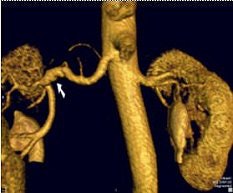

| Coronal 3D volume rendered from CEMRA in a 54-year-old man with uncontrolled hypertension. By acquiring images over a large field-of-view on a high-resolution matrix, the arteries of the entire abdomen, pelvis, and lower thorax are visualized in detail. |